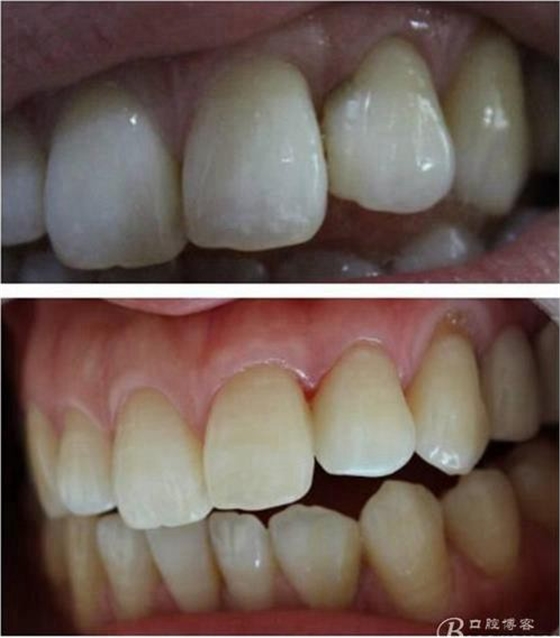

(這個是這個是學(xué)后第一次做美學(xué)修復(fù))

第一次做嵌體是樹脂嵌體。做完之后我跟我們主任炫耀,本來是想讓他夸我一下的。沒想到他說:“別高興太早,咱們時間上看。”說實話當(dāng)時心里一點底沒有,到底能用多長時間,自己一點沒底。